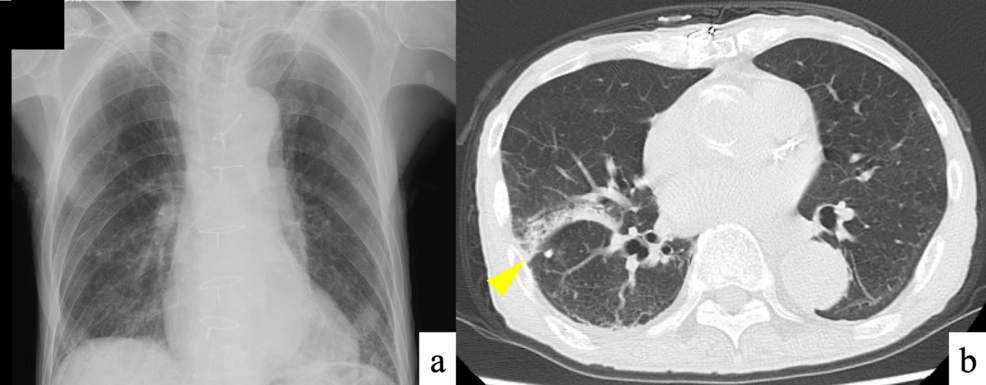

Diagnosis: Confirming PCP

Diagnosing PCP requires a high index of suspicion, especially in patients on chronic steroid therapy. Common diagnostic methods include:

- Induced Sputum: Microscopic examination of induced sputum samples for Pneumocystis cysts and trophic forms. Sensitivity can be variable.

- Bronchoalveolar Lavage (BAL): Considered the gold standard. Fluid obtained from the lungs is examined microscopically and with PCR.

- PCR Testing: polymerase Chain Reaction (PCR) assays are highly sensitive and specific for detecting Pneumocystis DNA in respiratory samples.

- Blood Tests: Elevated levels of serum (1→3)-β-D-glucan may suggest fungal infection, but are not specific to PCP.Keywords: PCP diagnosis, bronchoalveolar lavage, PCR testing, (1→3)-β-D-glucan, sputum analysis.